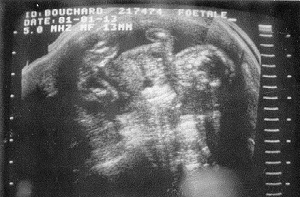

Je suis allée voir un gynécologue, et c'est lui qui m'a appris froidement et

durement, que mon bébé était atteint d'anencéphalie. Il m'a montré l'échographie

et m'a expliqué que la tête n'avait pas la taille normale. Je restais dans mon

Le seul souvenir de ta présence

C'est ton bracelet d'hôpital et mon échographie que je garde précieusement.